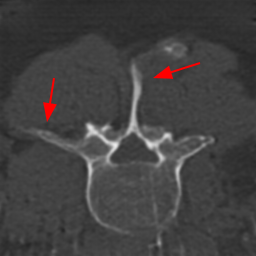

Disentanglement and explicit shape constraints. As shown in Fig. 4, we can see streak metal artifacts nearly everywhere in . M1 can roughly disentangle artifacts and anatomical information but strong vertical artifacts and strange air area appear in (see red arrows of M1 in Fig. 4). For the anatomical structure, M1 learns to segment vertebrae with fully supervised and applied on various CT images, but fails to suppress the false bony structure in and as may misclassify some metal artifacts as bone.

Implicit shape constraints. With , all segmentations are improved with higher Dices and smaller ASDs, see Table 1. As shown in Fig. 4, , and become similar but the high density bone is not correctly segmented in as it maybe treated as metal artifacts. Comparing between M2 and M1, the abnormal air region disappears but metal artifact reduction performance is still not satisfactory.

Anatomy-aware generation. With AADE layer in M3, , and are substantially improved as shown in Table 1. Note, is used as attention map, so we do not expect it to be identical to . In , metal artifacts are further suppressed comparing with M2. Thus, AADE is critical to our anatomy-aware artifact disentanglement framework. With the special structure, can be punished in the image translation and reconstruction processes and the other encoders and generators receive more guidance. However, as shown by blue arrows in Fig. 4, we observe a shadow of vertebra edge of appears in of M3 and the vertebra boundaries get smoothed out in . It may be because sharp edges are encoded as metal artifacts and forced to be added to by artifact consistency loss .

Removal of . To mitigate vertebrae shadows, we remove . The segmentation performance of most images in M4 gets improved because of better synthetic images. Overall, in M4 yields the best segmentation performance for CBCT images with an average Dice of 0.847 and an average ASD of 1.54 mm. For the synthetic images, M4 generates with the best quality and least metal artifacts among all the models. M4 also outputs without vertebra shadows. The results indicate our shape-aware network could preserve anatomical details and transfer the metal artifacts precisely without .